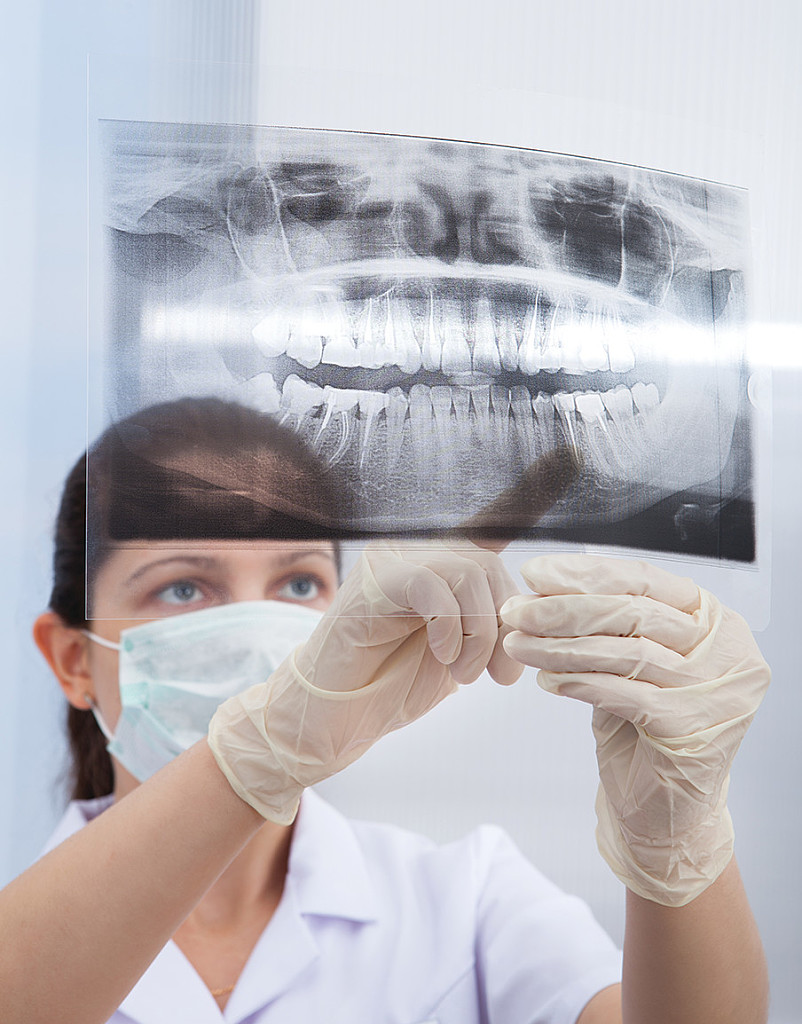

If your family history includes the need for orthodontic solutions or impacted wisdom tooth removal services, chances are that you will need them, too. X-rays or digital imaging can determine the positioning of wisdom teeth and the likelihood of issues coming up, while braces will help correct misaligned teeth.